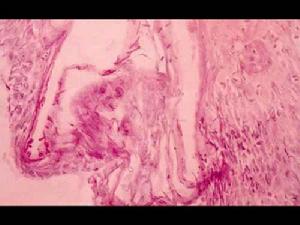

念珠菌病根據不同器官和發病階段,組織病理改變可呈炎症性(如皮膚、肺)、化膿性(如腎、肺、腦)或肉芽腫性(如皮膚)。特殊臟器和組織還可有特殊表現,如食道和小腸可有潰瘍形成,心瓣膜可表現為增殖性改變,而急性播散性病例常形成微膿腫,膿腫內可見芽孢和菌絲,其外有中性粒細胞和組織細胞浸潤。芽孢外圍偶見嗜伊紅樣物質,類似星狀體。菌絲有時侵入血管壁,病理組織中發現菌絲體有診斷價值,但必須與曲菌、毛霉和蛙糞霉鑑別。